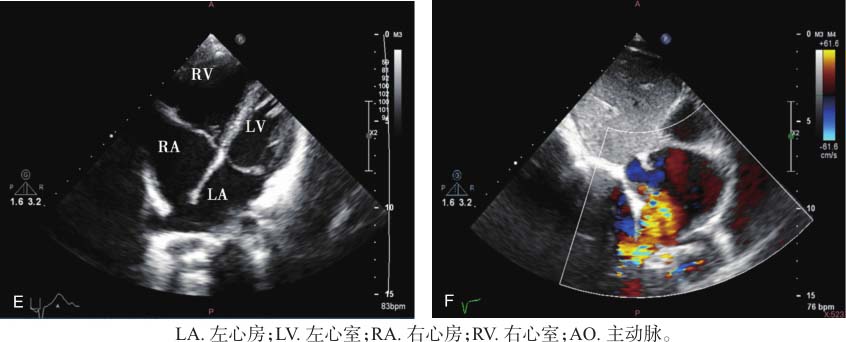

图22-1 患儿超声心动图表现

A.左心室长轴切面显示右心房及右心室增大;B.四腔心切面显示右心房及右心室增大,三尖瓣少量反流;C.三尖瓣反流频谱估测肺动脉压力;D.非标准四腔心切面彩色多普勒显示右中肺静脉回流入右心房;E.二维超声非标准四腔心切面显示房顶部房间隔缺损;F.剑突下双心房切面彩色多普勒显示心房水平左向右分流。

本病例左心室长轴切面显示右心房及右心室明显增大,提示存在左向右分流可能。非标准四腔心切面可进一步明确房间隔缺损及肺静脉异位引流至右心房。部分型肺静脉异位引流合并房间隔缺损时,分流量较单纯房间隔缺损或部分型肺静脉异位引流大。此类部分型肺静脉异位引流可于斜四腔心切面直接观察到肺静脉回流途径,相对不易漏诊和误诊。